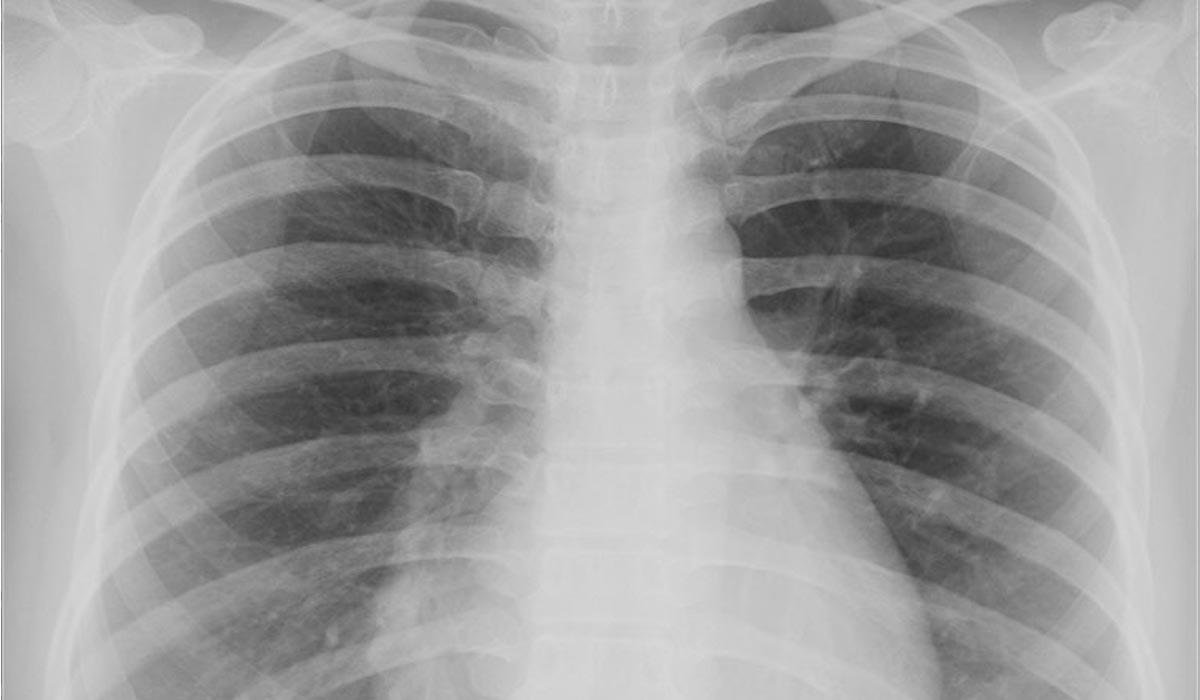

Halk arasında ak toprak, çorak toprak, gök toprak, çelpek, höllük veya ceren toprağı gibi isimlerle de bilinir. Asbest liflerinin solunması mezotelyoma, asbestozis ve akciğer kanseri dahil olmak üzere çeşitli tehlikeli akciğer rahatsızlıklarına yol açabilir. Bu nedenle artık ciddi bir sağlık ve güvenlik tehlikesi olarak kötü bir üne sahiptir.

Asbestozis ise asbestos solunmasıyla oluşan toz hastalığıdır.